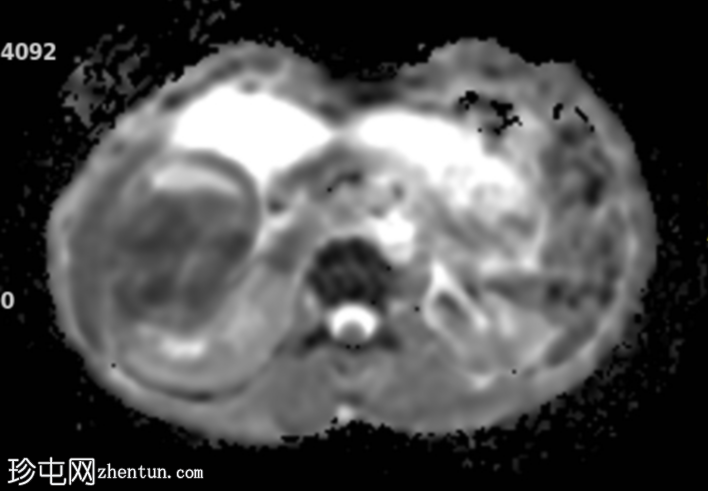

轴位

DWI序列

再次观察到上述肾前部外生性病变,其实性成分在T1加权像上呈等高信号,在T2加权像上呈低信号,伴有碎片扩散受限和低ADC值(化脓性物质)。囊性成分内部可见液-碎片/脓液界面。可见内部低信号结石。可见肾周模糊影。该病变压迫并可能侵犯右肾盂,导致中度肾积水。

病灶不规则的低信号,以及液-液界面伴有碎屑(可能为化脓性物质)扩散受限和肾周模糊,再次高度提示炎症性病变(黄色肉芽肿性肾盂肾炎,XGP),而非可能性较小的肿瘤。